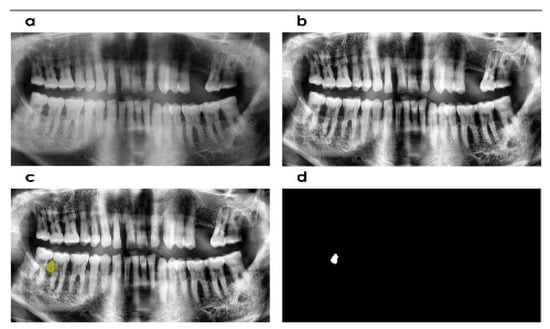

2.2. Computational Tool

2.3. Image Enhancement

2.4. Localization and Angle Estimation

2.5. Segmentation